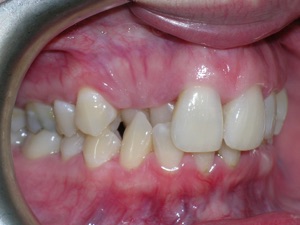

This case was of a young lady who desperately wanted Invisalign, but had been told it was not possible. There was not one, but two teeth that had come in toward the roof of the mouth.

And more.

Needless to say, we were both quite happy with the outcome. Using elastics we were able to push back the back teeth and create space for the two teeth stuck behind.